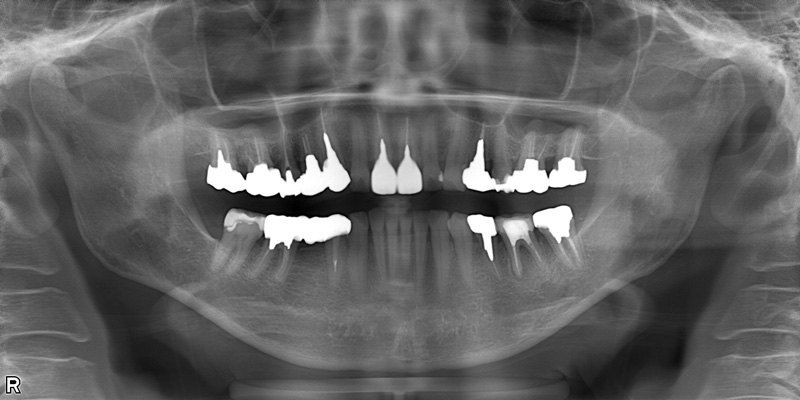

58歳女性

治療前

治療後

| 施術名 | インプラント治療 |

| 施術の説明 | インプラント治療とは、歯を抜いた所にチタン製の人工歯根を埋入し、新しく歯を入れる方法です。 |

| 施術の副作用 (リスク) | 腫れや疼痛を感じる、違和感を感じるなどの症状を生じることがあります。 |

| 施術の価格 | 53万円~+消費税 |